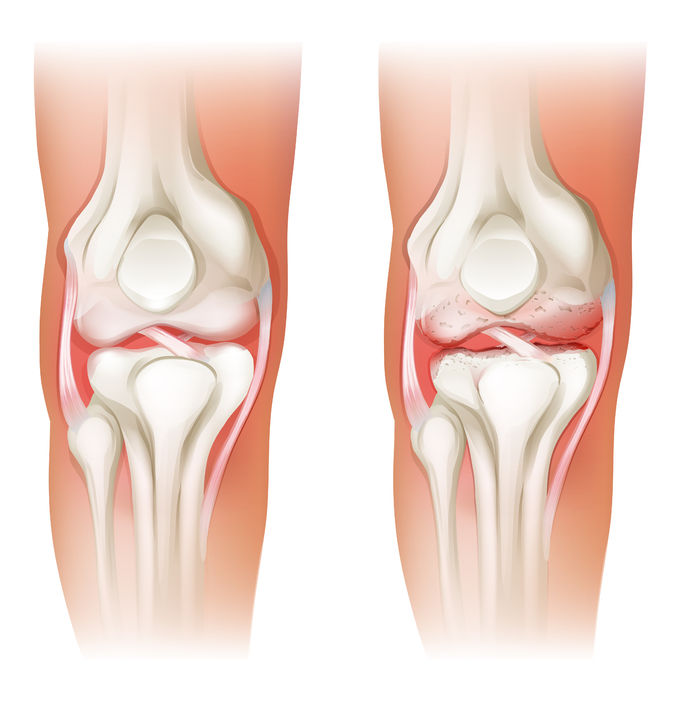

Artrose is een aandoening aan één of meerdere gewrichten. Een gewricht bestaat uit twee botuiteinden waar kraakbeen overheen zit. Kraakbeen is belangrijk omdat het schokken opvangt en omdat het ervoor zorgt dat u zich soepel kunt bewegen.

Rondom het gewricht zitten het gewrichtskapsel en de gewrichtsbanden. In dat gewrichtskapsel zit een soort smeermiddel dat ervoor zorgt dat het gewricht zijn werk doet. Bij artrose wordt het gewrichtskraakbeen dunner en neemt de kwaliteit ervan af. Het gewricht kan dikker aanvoelen door een uitstekend bot of door een gezwollen gewrichtskapsel. Hierdoor worden bewegingen pijnlijk en je krijgt de neiging om het gewricht steeds minder te gaan bewegen. Dit veroorzaakt weer dat je stijf wordt en dat je spieren slapper worden.